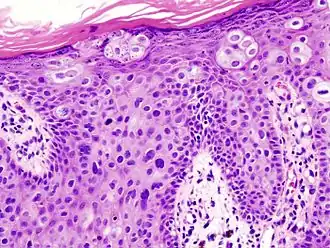

In situ disease

Bowen's disease is essentially equivalent to and used interchangeably with cSCC in situ, when not having invaded through the basement membrane.[12] Depending on source, it is classified as precancerous[13] or cSCC in situ (technically cancerous but non-invasive).[48][49] In cSCC in situ (Bowen's disease), atypical squamous cells proliferate through the whole thickness of the epidermis.[12] The entire tumor is confined to the epidermis and does not invade into the dermis.[12] The cells are often highly atypical under the microscope, and may look more unusual than the cells of some invasive squamous-cell carcinomas.[12]

cSCC in situ, high magnification, demonstrating an intact basement membrane.[12] -

cSCC in situ -

cSCC in situ